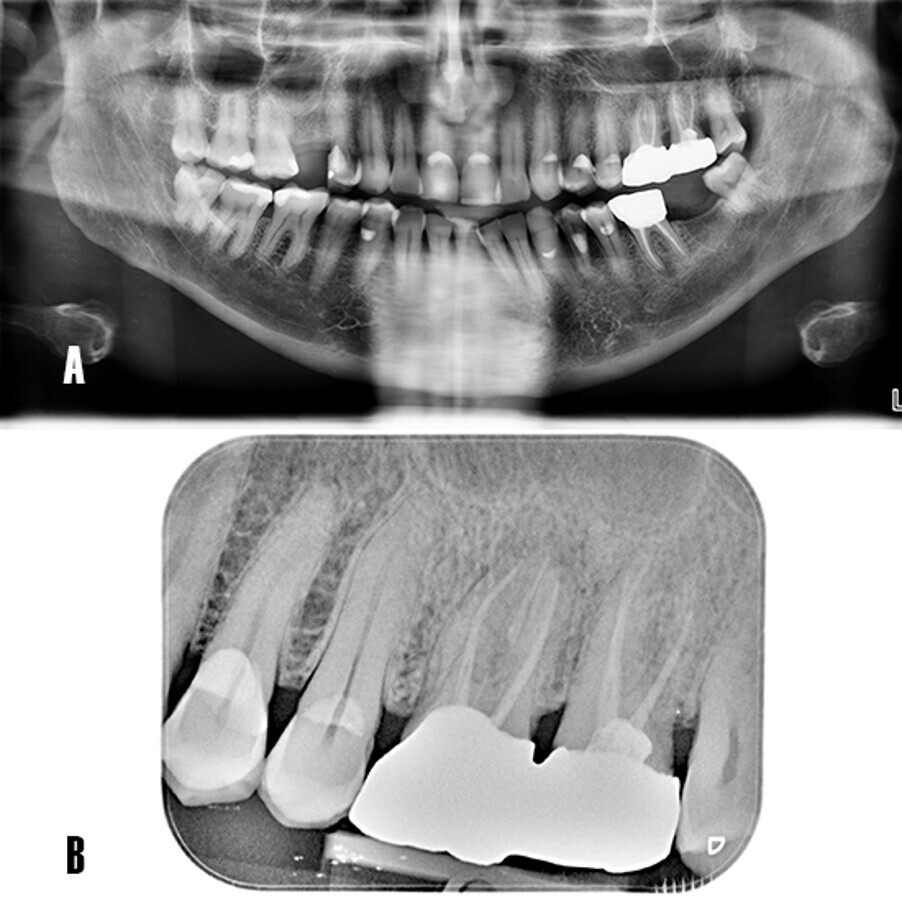

Tras realizar la evaluación radiológica bidimensional, en la ortopantomografía se observa los dientes 2.6 y 2.7 endodonciados y ferulizados mediante prótesis fija cementada (Fig. 2A). La radiografía periapical no evidencia una radiotransparencia bien definida a nivel apical. Las crestas alveolares interproximales se observan íntegras con bordes corticalizados bien definidos (Fig. 2B).

Fig. 2

Figura 2. Evaluación radiológica bidimensional. A) La ortopantomografía advierte el tratamiento de conductos a nivel 26 y 27, portadores de prótesis fija metal-cerámica. B) La radiografía periapical muestra los dientes 26 y 27 endodonciados, se observa una imagen radiotransparente poco definida en apical de 26.